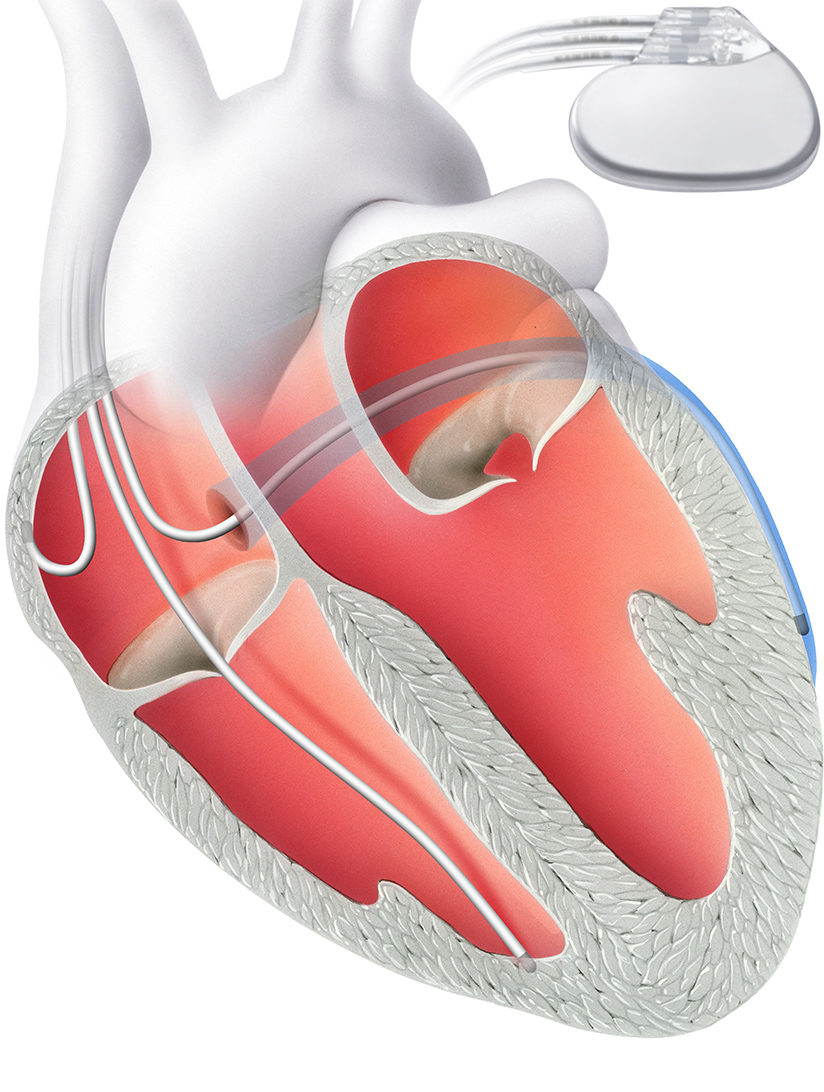

Als Alternative ist seit knapp 10 Jahren der subkutane ICD (S-ICD) verfügbar. Bei dieser Therapieform bleiben Herz und Blutgefässe unangetastet: eine Elektrode wird nicht unmittelbar ins Herz implantiert, sondern oberhalb des Brustbeins direkt unter die Haut („subkutan“). Somit ist das Risiko für Elektrodenkomplikationen sowie Komplikationen während einer möglichen Elektrodenentfernung deutlich reduziert. Allerdings ist das Risiko für sog. „inadäquate Schockabgaben“ („Fehlschocks“) leicht höher, als bei den Standard ICDs mit Elektrode im Herzen.

Als Alternative ist seit knapp 10 Jahren der subkutane ICD (S-ICD) verfügbar. Bei dieser Therapieform bleiben Herz und Blutgefässe unangetastet: eine Elektrode wird nicht unmittelbar ins Herz implantiert, sondern oberhalb des Brustbeins direkt unter die Haut („subkutan“). Somit ist das Risiko für Elektrodenkomplikationen sowie Komplikationen während einer möglichen Elektrodenentfernung deutlich reduziert. Allerdings ist das Risiko für sog. „inadäquate Schockabgaben“ („Fehlschocks“) leicht höher, als bei den Standard ICDs mit Elektrode im Herzen.

Ursache, aber auch Folge einer Herzschwäche ist die sogenante Dyssynchronie. Dabei werden die linke und die rechte Herzkammern nicht mehr gleichzeitig, sondern zeitversetzt zum Schlagen stimmuliert. Diese Dyssynchronie führt dazu, dass die Pumpleistung nicht mehr effektiv ist, und sie verschlimmert selber noch die Herzschwäche (Teufelskreis).

Synchronie verbessern

Eine kardiale Resynchronisationstherapie (CRT) korrigiert dieses Problem. Sie hat zum Ziel, die Synchronie der linken und rechten Herz-Hauptkammern zu verbessern. Hierzu wird ein biventrikulärer, also beide Herzkammern stimulierender Herzschrittmacher implantiert.

Dieser umfasst nicht wie ein herkömmlicher Herzschrittmacher zwei Elektroden, sondern drei. Die zusätzliche Elektrode wird in eine Koronarvene vor der linken Herzkammer eingesetzt. Alternativ kann sie über einen thorakoskopischen Zugang, einem minimalen Schnitt in den Brustkorb, eingesetzt werden.

Dank dieser dritten Elektrode ist es möglich, beide Herzkammern gleichzeitg zu stimulieren. Für den Eingriff ist ein Spitalaufenthalt von zwei bis drei Tagen nötig.